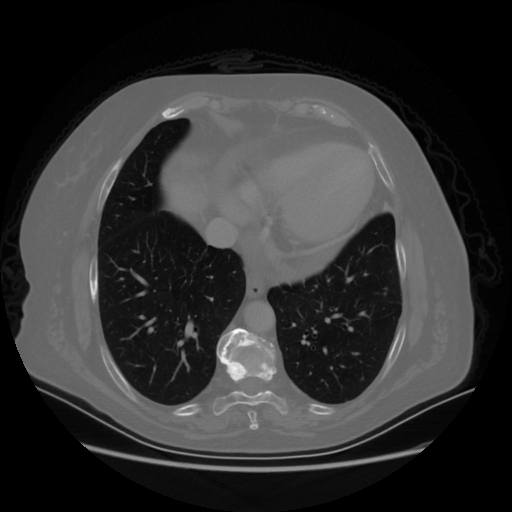

Reconstructed NATIVE CT scan (cycle consistency)

Full window (WL 1023.5, WW 4095 β†’ Low βˆ’1024, High +3071)

Lung window (WL -600, WW 1500 β†’ Low βˆ’1350, High +150)